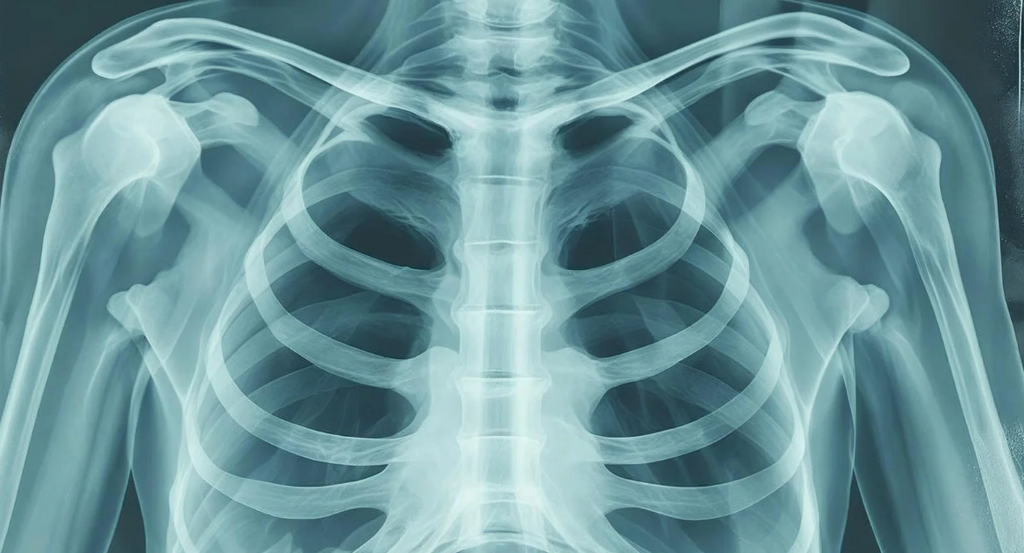

組織損傷の程度を把握するために画像読影は必要です

骨折や損傷を指摘する医師による診断のための読影ではなく、理学療法士や作業療法士に必要な運動機能評価として、画像読影はとても有用なツールなのです。そのために必要な知識を若手理学療法士や作業療法士にわかりやすく解説するセミナーをご紹介しましょう

回復期で働いているときは脳血管疾患の患者様だけでなく、神経難病のような患者様に対してのリハビリを担当する機会は多いのではないでしょうか。  私自身も回復期で働いているときは、療養病棟で患者様の離床を促したりすることは多かったことを記憶しています。 こうした患者様は原疾患だけでなく、基礎疾患として様々な疾患を有していることが多く、特に内科系疾患の知識は欠かせませんでした。 そんななかでも呼吸機能をいかに評価すべきかという知識は特に欠かせません。 その理由について今日は考えてみたいと思います。   回復期リハで働くなら呼吸機能のチェック技能が必須な理由とは? 運動器疾患の方でも、心疾患や呼吸器疾患を既往にもつ方は多いと思います。 心疾患を合併している場合には、呼吸器にも影響を及ぼす可能性も高くなります。 脳卒中片麻痺で呼吸筋に影響をすることもあります。 嚥下機能にも影響することもあります。誤嚥をしてしまう方もいます。 何気なくリハビリをしている目の前にいる患者様の呼吸に本当に問題はないでしょうか?   説教的にリハビリを進めていきたいと考えている。 でもなかなかうまく進まないということは多いと思います。   患者様が疲れてしまってうまく進まない 息切れや易疲労性が問題になる こうした問題に対してリハビリを進めるためには呼吸機能の評価は必須です。 回復期で状態が安定しているからこそリスク管理を徹底しよう   回復期に入った患者さんは一見安定しているように見えますが、「病状が安定している=リスクが少ない」という思い込みは非常に危険です。 たしかに急性期と比べて状態は落ち着いているように見えるかもしれませんが、実際には胸部レントゲンや心電図などの明確な異常所見が乏しく、医学的な情報が少ないのが現実です。   さらに、リハビリの時間が延び、運動負荷も徐々に増していくため、細やかな観察と判断が不可欠です。この時期こそ、患者さん自身が発している小さなサインを見逃さずに拾う「フィジカルアセスメント」の重要性が増します。 客観的データに頼りにくいからこそ、症状の変化に気づく力が問われるのです。   たとえば、労作性狭心症やNYHA Class Ⅲ程度の心不全では、安静時には症状が出ないことが多く、病室で静かにしているだけでは問題が表面化しません。...